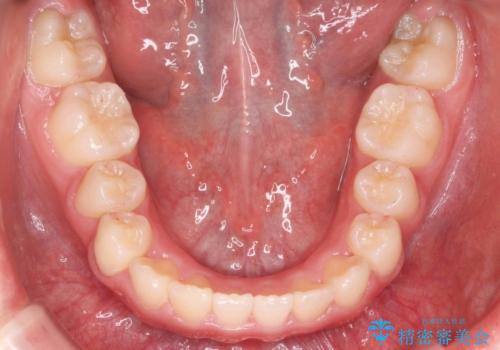

八重歯 歯を抜かずにインビザラインで

- 八重歯を主訴に来院。

抜かずに歯を少し削って入れる方法で並べました。

10代のうちに矯正をしておくと歯の移動は簡単で、歯ぐきも下がりにくいです。

乳歯が永久歯に生え変わるまで成長観察を続け、永久歯列になってから治療開始しています。